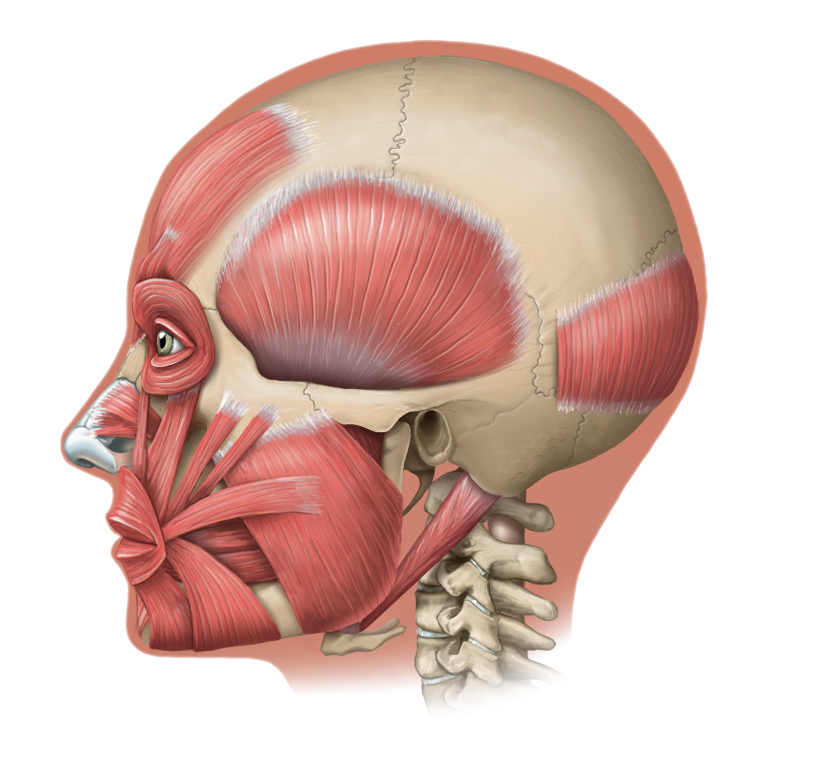

Medical Illustration

All images are works made for hire and are the exclusive property of the client. These are shown as sample purposes of my work only. For licensable work, please see my Illustration Services page.

Contract freelancer for many others, some examples of my work below.